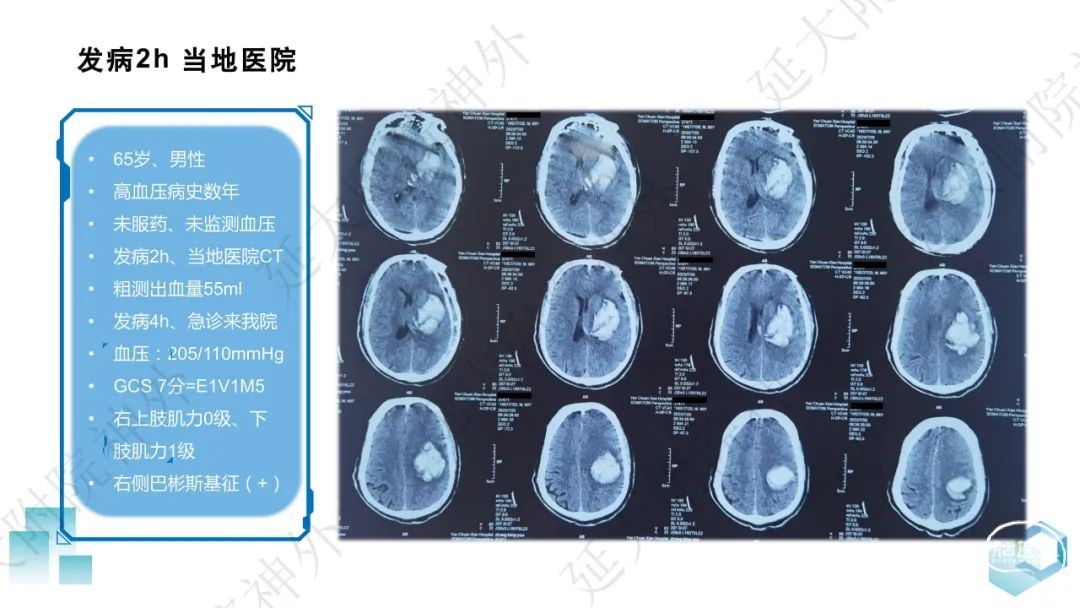

今天为大家分享的是《监测有道丨颅脑创伤-神经重症周刊》第332期,由延安大学附属医院神经外科贾云峰主任医师带来的:左侧基底节区出血破入脑室一例神经内镜下血肿清除术,欢迎阅读、分享。